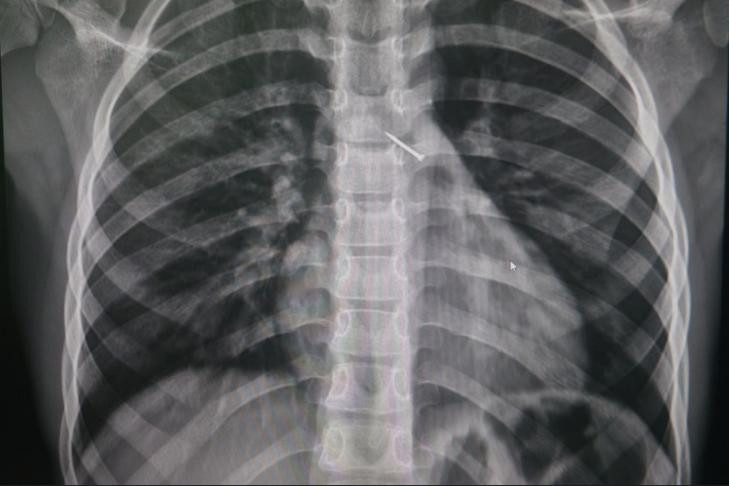

Фото: Министерство здравоохранения Новосибирской области

Обследование показало, что канцелярская кнопка попала в бронхи, уперлась в одну из стенок и вызывала локальное воспаление. Опасный предмет успешно достали с помощью эндоскопических зажимов, — говорится в сообщении министерства здравоохранения Новосибирской области.